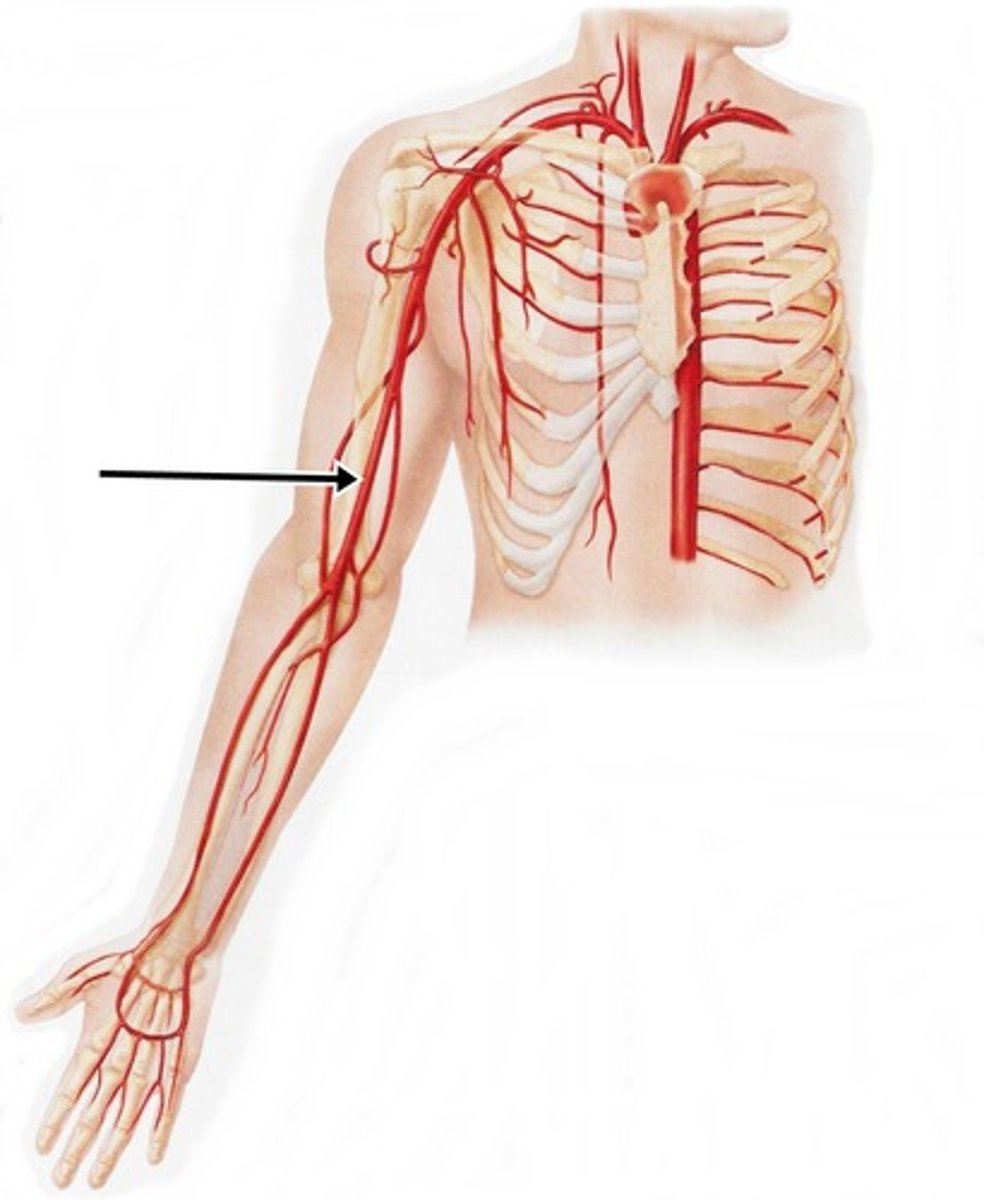

axillary artery

flows into axilla, lateral chest, and shoulder joint

brachial artery

flows into radial and ulnar arteries

radial artery

serves the lateral forearm, wrist, thumb, and index finger

ulnar artery

serves the medial forearm and digits 2-5